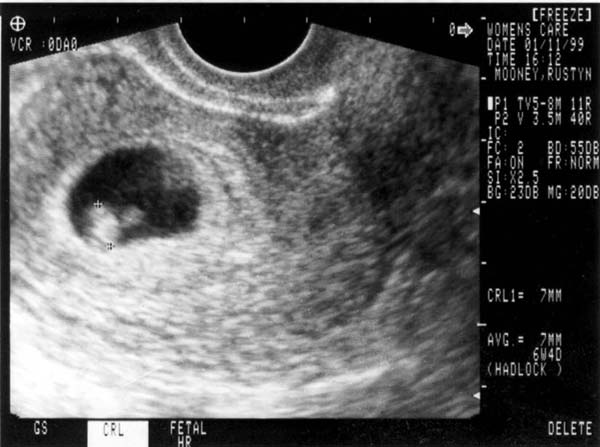

Here's a picture of the first sonogram, taken January 1999.

1st Sonogram

That's our little embryo there at 8 weeks, with a little yolk sack growing outside the main body. That's were the intestines develop until they sink into the body cavity.